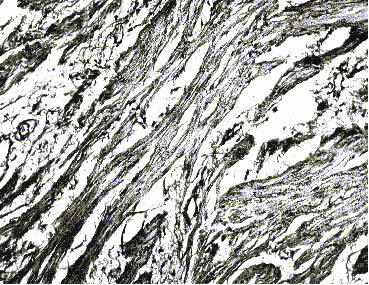

7 сутки (Отек интерстиция, очаговая гиперплазия

уротелия)